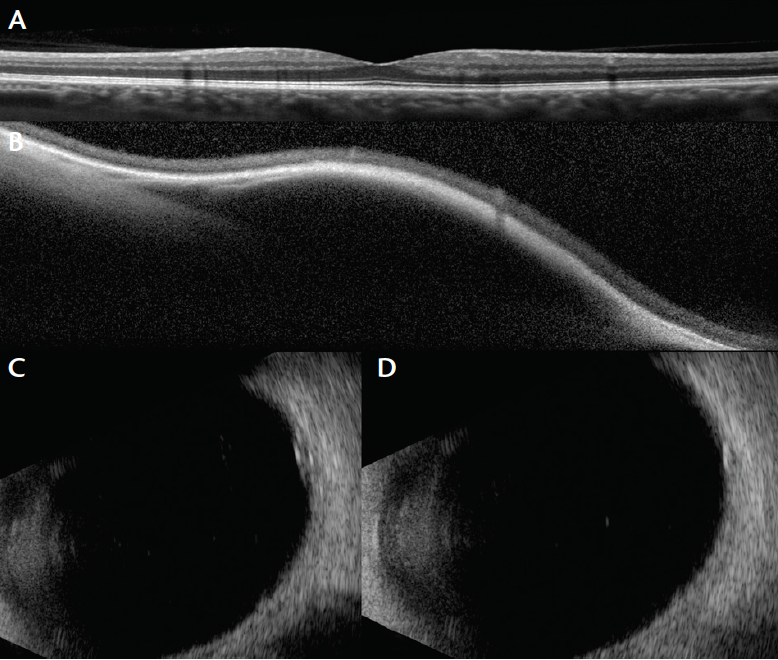

Figure 2. OCT of the patient’s left eye demonstrated intact macula and no subretinal fluid (A). OCT through lesion showed internal hyporeflectivity with smooth surface, consistent with VVV (B). B-scan ultrasonography showed inflated varix upon gaze toward the lesion (C) and deflation on primary gaze (D).

OCT showed an intact macula with no retinal edema or subretinal fluid (Figure 2A). Furthermore, OCT of the dilated mass revealed the smooth walls of the vascular ectasia within the choroid (Figure 2B). There was no solid component. Ultrasound confirmed gaze-evoked inflation (Figure 2C) and deflation upon primary gaze (Figure 2D). The patient was counseled on the benign nature of his diagnosis, and we advised him to attend annual monitoring visits.